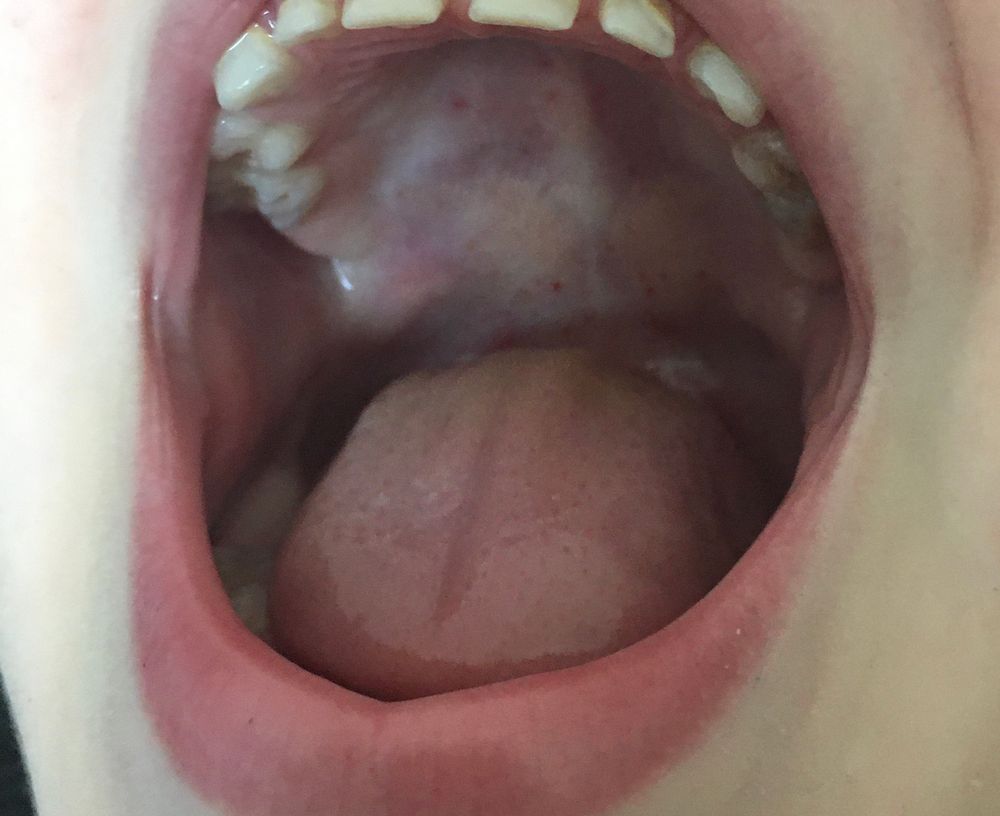

Здоровье.У сына заметила на ступнях, внутренней стороне бёдер и во рту непонятную сыпь, которую раньше не встречала. Вчера была температура 38,7. Сбила и больше не поднималась. Знает ли кто-нибудь что это за сыпь? Коксаки? К врачу в понедельник пойдём.

У нас с такими симптомами был вирус Коксаки.Ночью или поздно вечером очень сильно плакали, как потом выяснилось при этом вирусе сильно болит голова.

Kat, голова вроде не болела, сейчас все прошло, кроме сыпи во рту, там ещё сильнее стала. Зато у дочки поднялась температура 39,5 🤦♀️